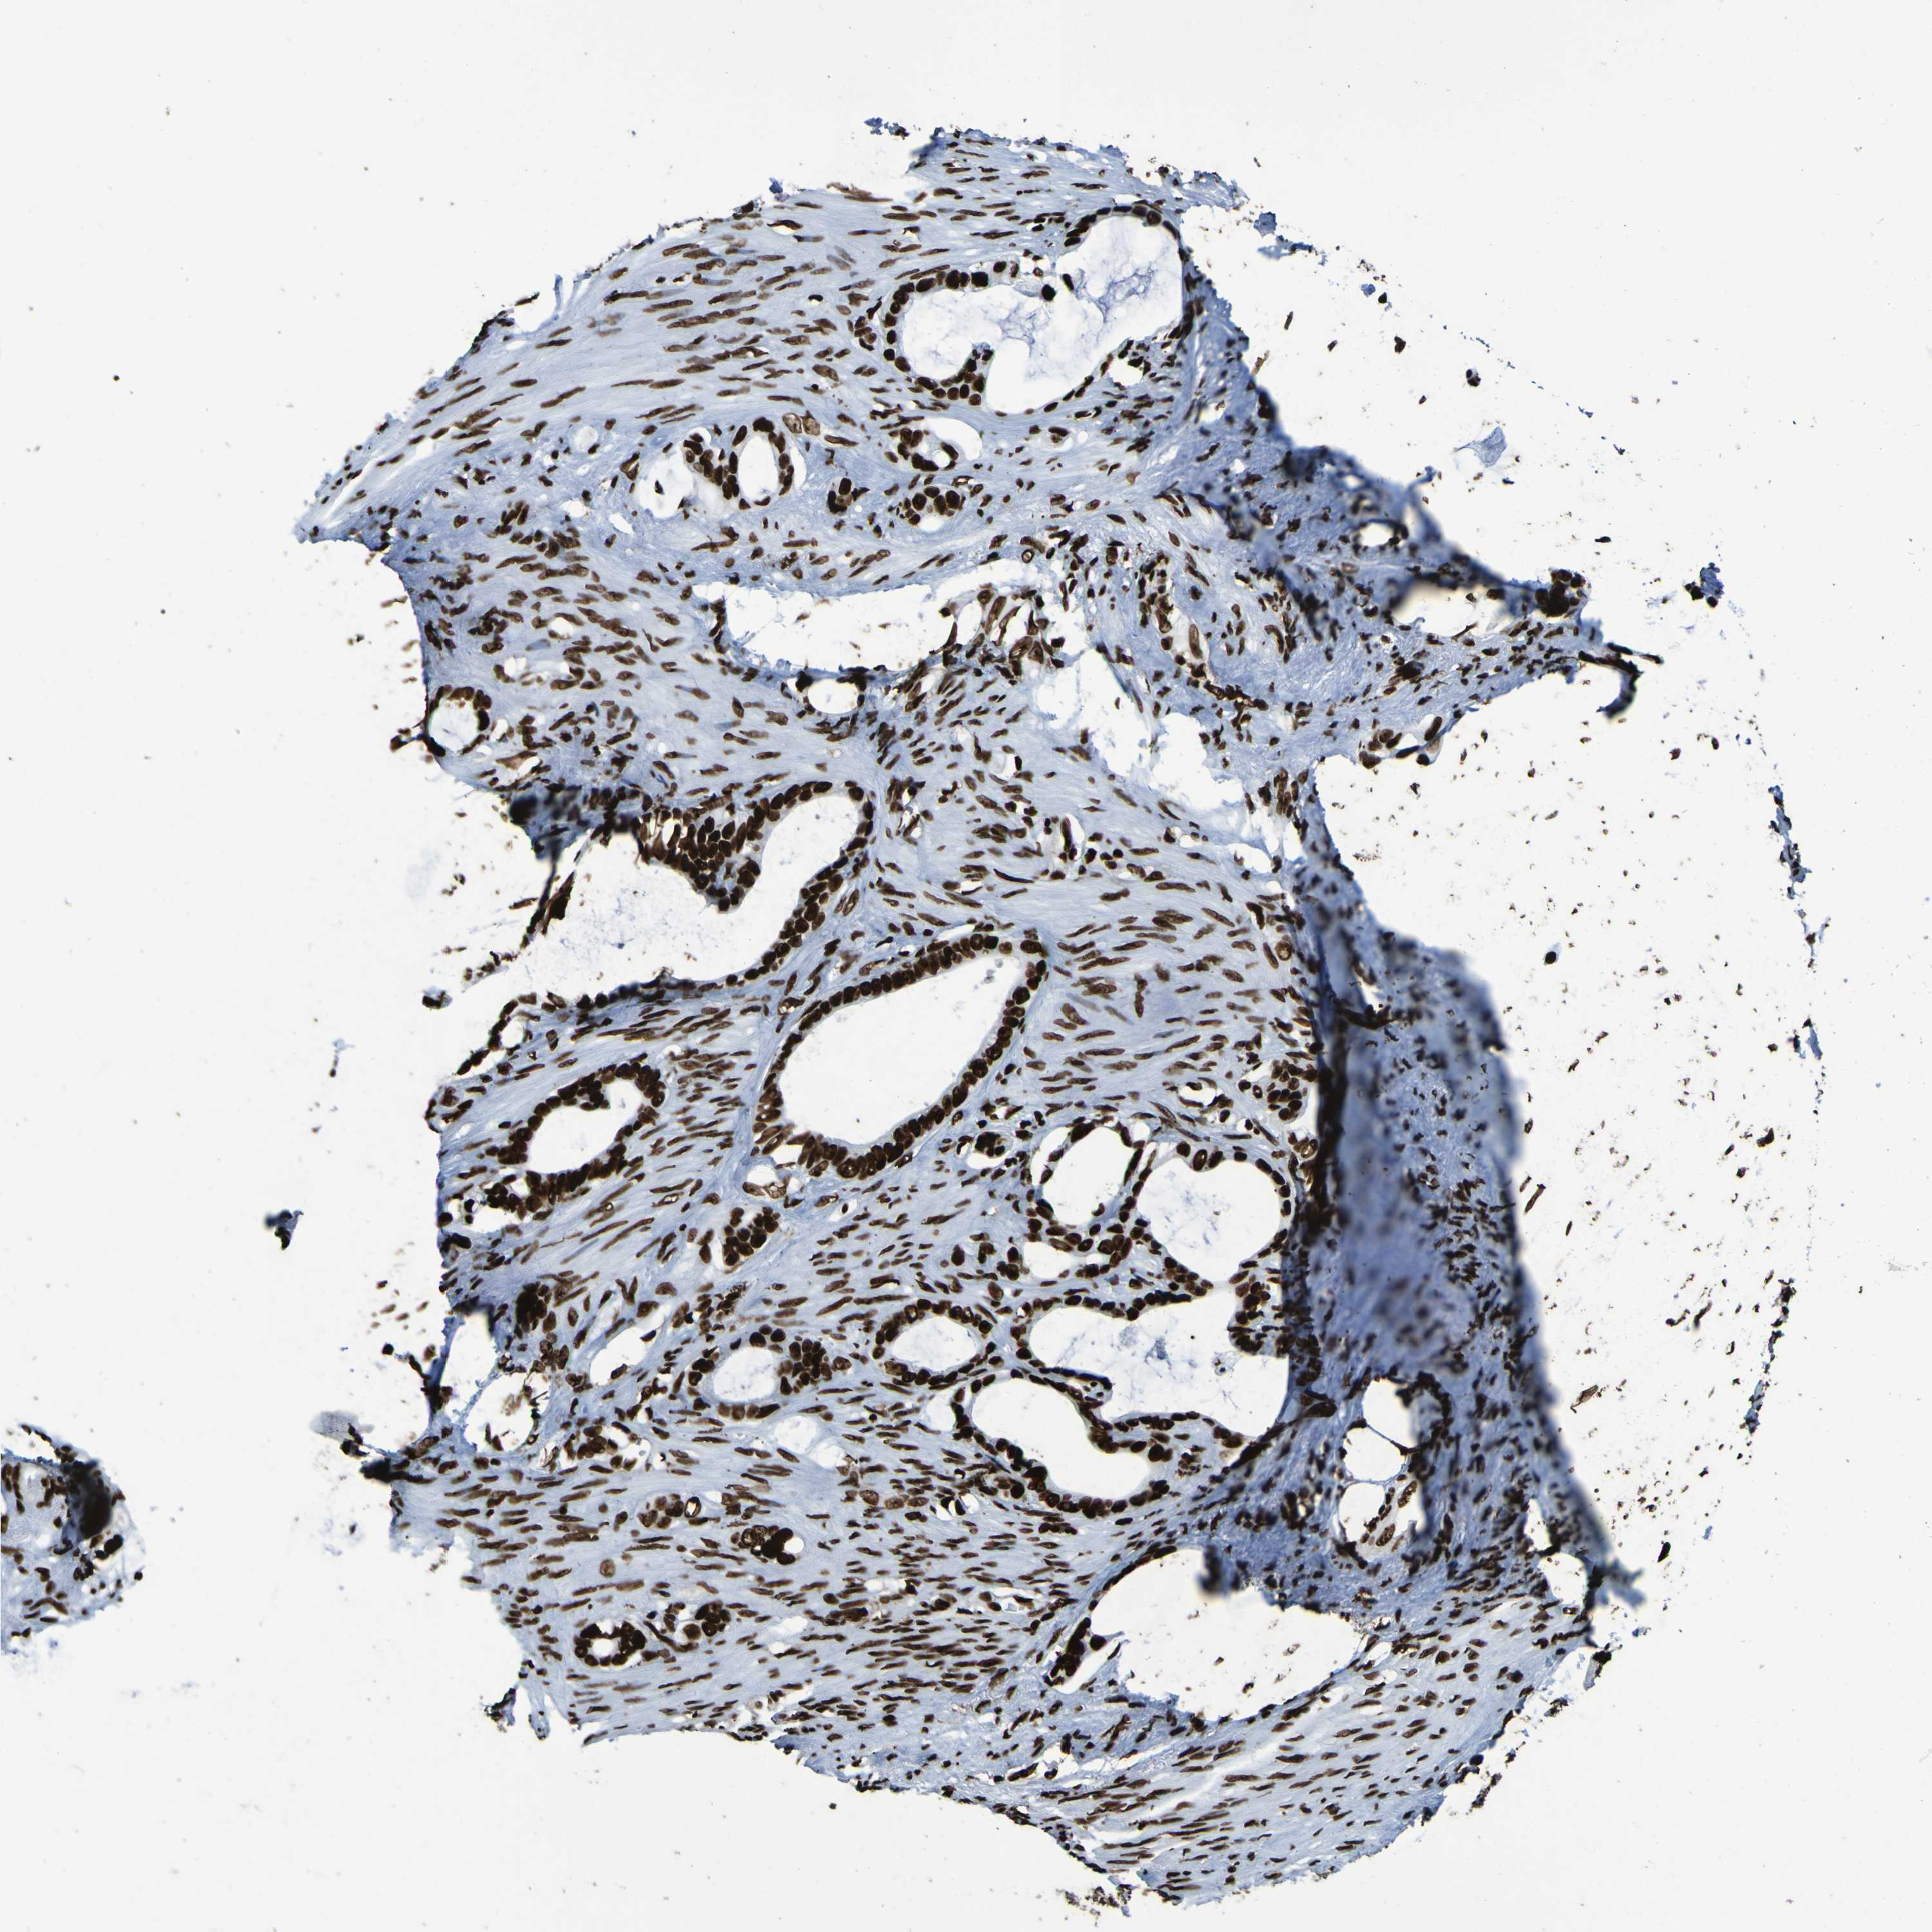

STOMACH CANCER - Protein expressioni

A mouse-over function shows sample information and annotation data. Click on an image to view it in a full screen mode. Samples can be filtered based on level of antibody staining by selecting one or several of the following categories: high, medium, low and not detected. The assay and annotation is described here.

Note that samples used for immunohistochemistry by the Human Protein Atlas do not correspond to samples in the TCGA dataset.

Antibody stainingi

Antibody staining in the annotated cell types in the current human tissue is reported as not detected, low, medium, or high, based on conventional immunohistochemistry profiling in selected tissues. This score is based on the combination of the staining intensity and fraction of stained cells.

Each image is clickable and will lead to virtual microscopy that enables deeper exploration of all samples and also displays staining intensity scores, fraction scores and subcellular localization as well as patient and tissue information for each sample.

Antibody HPA011384

Antibody CAB012983

Staining

High

Medium

Low

Not detected

Intensity

Strong

Moderate

Weak

Negative

Quantity

>75%

75%-25%

<25%

None

Location

Nuclear

Cytoplasmic/membranous

Cytoplasmic/membranous,nuclear

Adenocarcinoma, NOS

Adenocarcinoma, High grade